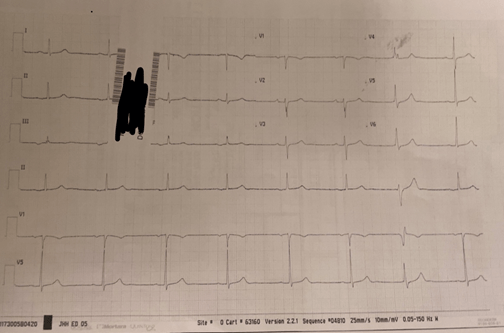

- ECGs from consult and 2019 reviewed (see below) and discussed – ? pre-excitation